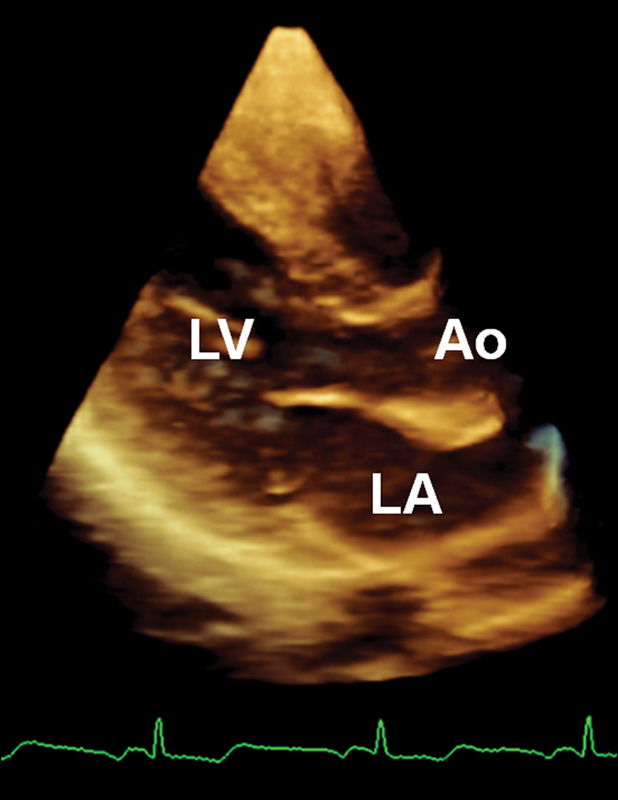

فحوصات تشخيصية لبعض امراض القلب والشرايين التاجية